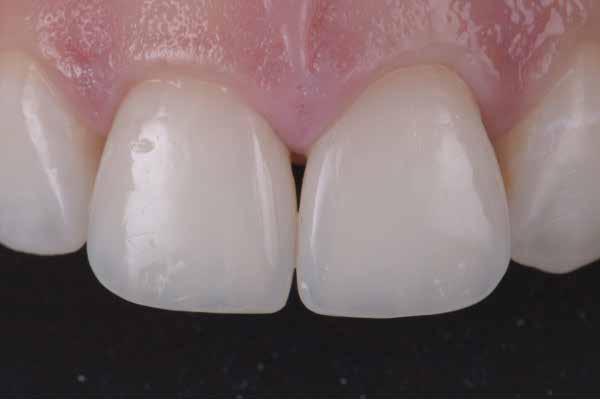

2-4. ábra: Gyakori problémák klasszikus megközelítéssel. 5. ábra: Tökéletes vészhelyzeti profil elülső szárnyas technikával. Dr. Jun Iwata, Japán jóvoltából.

2. eset: Egyszínű restauráció egy mikrodiasztémán, ahol a viasz nem kivitelezhető (1 óra ülésidő)